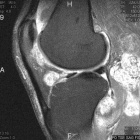

43 y/o male w 5 years of chronic R knee pain, worsening over the past 3 years. Feels like “crunching marbles”. Pain at night and worse with activity. No weight loss, fevers/chills. No systemic complaints.

PE: R knee effusion; crepitus, palpable masses near popliteal fossa, mild dec R knee ROM secondary to pain, neurovascularly intact, 5/5 motor.